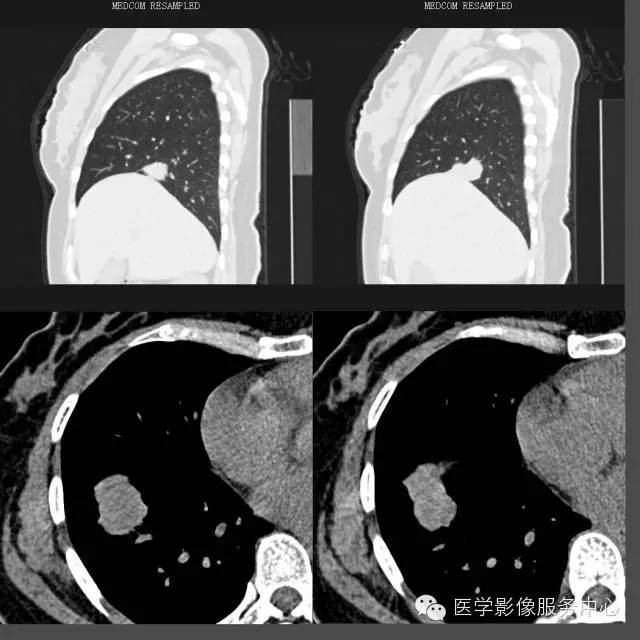

CT上表现的结节或肿块影像在病理组织学上为肿瘤的乳头状结构,以及破坏、扭曲的肺组织;磨玻璃样阴影代表肿瘤细胞沿肺泡壁生长或阻塞肺泡腔引起的阻塞性肺炎;

肺乳头状腺癌生长方式与肺泡癌相似,结节或肿块影周围出现的卫星灶能对应病理组织学上的阻塞性肺炎、支气管炎、细支气管脓肿等改变。这种磨玻璃样改变在肺腺癌病例中普遍可以看到,但在其他类型肺癌中比较少见。

空洞、钙化在肺乳头状腺癌中几乎见不到。

“空泡征”、“空气支气管征”在肺乳头状腺癌病例中大部分可以看到,但边缘光滑、境界清楚;而其他类型肺癌即使出现这些征象,其边缘境界往往不清楚,这一点是和其他类型肿瘤所不同的。

1、炎性假瘤:炎性假瘤大多发生肺的表浅部位,形态呈圆形、椭圆形或类圆形,大小在2~4cm,部分大于5cm,密度中等、均匀,边缘清楚,有时可见分叶状、尖角征及放射冠样表现。邻近胸膜见局限性粘连增厚,阻塞支气管部分出现阻塞性肺炎。肺门及纵隔未见肿大淋巴结。增强后呈快进慢出表现,部分呈慢进慢出改变。

2、结核瘤:可有肺癌的各种直接、间接征象,酷似肺癌,但周围通常有卫星病灶。通常增强后未见强化改变。